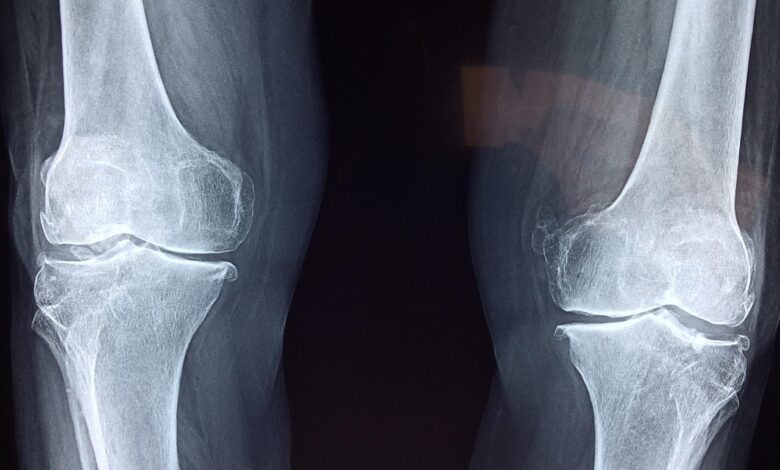

Laboratorijski testi so potrdili, da je “Bone 02” uspešno prestal merila za varnost in učinkovitost. V enem izmed poskusov je bil postopek zaključen v manj kot 180 sekundah ali treh minutah, medtem ko bi konvencionalne metode zdravljenja zahtevale večji rez za vstavitev jeklenih plošč in vijakov. Lepilo je bilo uspešno preizkušeno na več kot 150 pacientih. Zlepljene kosti so pokazale največjo vezno moč več kot 400 funtov, strižno trdnost približno 0,5 MPa in tlačno trdnost okoli 10 MPa, kar poudarja, da ima izdelek potencial za zamenjavo tradicionalnih kovinskih vsadkov. Znanstveniki so navedli, da bi lahko tudi zmanjšalo tveganja za reakcije in okužbe.